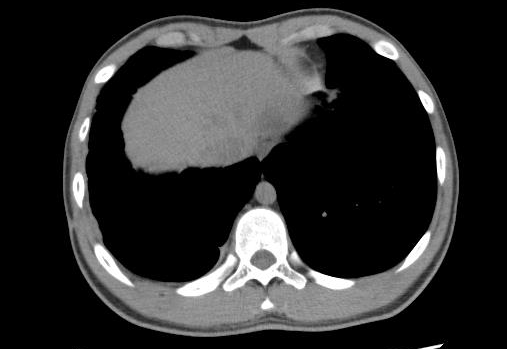

出院后,白某某坚持每月复查,规律用药。近日,在他术后整整一年的复查中,胸部CT清晰显示:原先的病变区域已显著吸收好转,右侧胸腔结构基本恢复正常,肺功能得到有效保护。